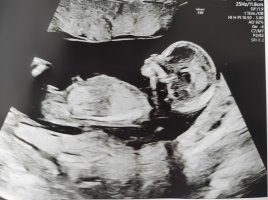

Nub-teoria

Noissa alemmissa ei näy mitään, mutta kyllä mä nyt sanoisin että poika. Nub on selkeä kyllä, mutta mua jännittää arvioida koska en tiedä jatkuuko se vielä tosta vai oisko koko nub nyt sit tossa kuvassa. 😁